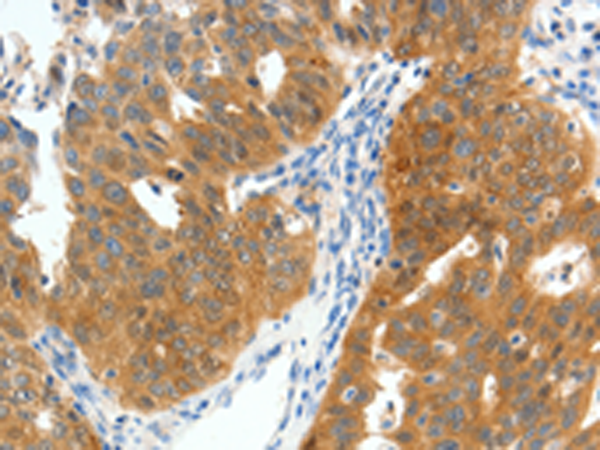

分类: 科研抗体货号: P11315别名: PDI, PDA2, PDIP, PDIR应用: IHC反应种属: Human